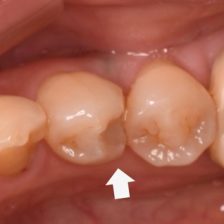

むし歯治療

根管治療

症例集